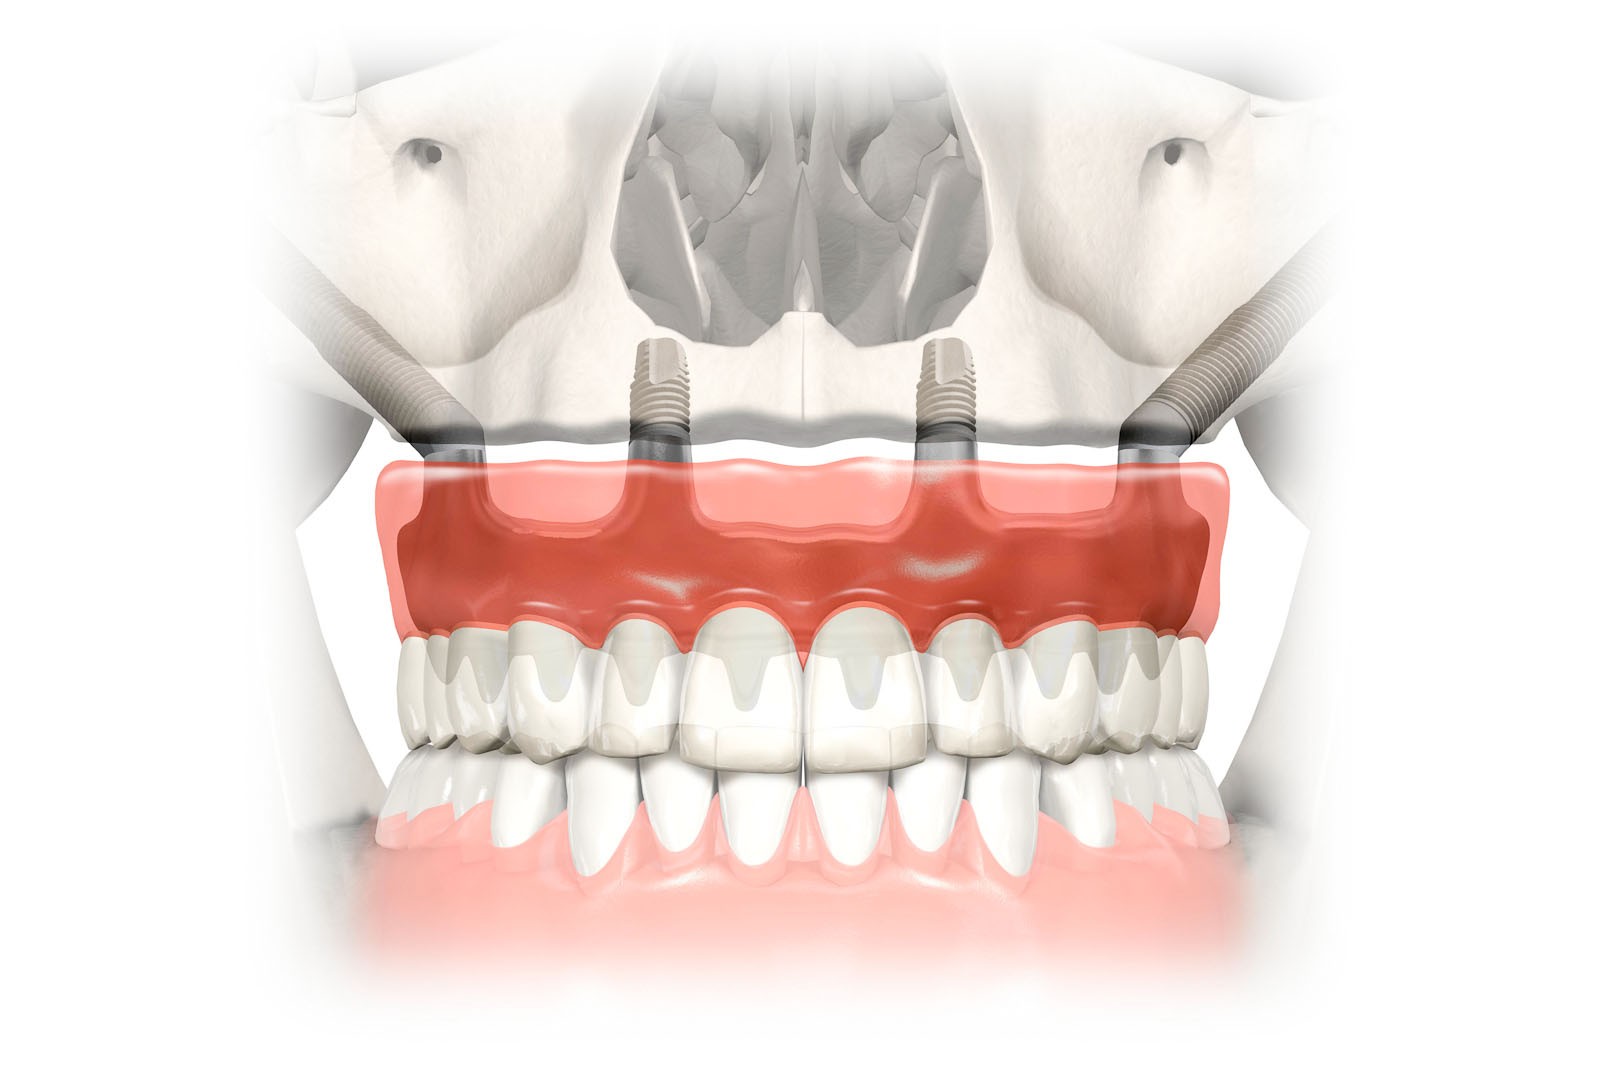

2 implanty jarzmowe, 2 lub 4 krótkie implanty korzeniowe, 4 lub 6 łączników MultiUnit, natychmiastowy tymczasowy most wykonany z akrylu, o ile jest to możliwe.

Przeznaczony dla pacjentów z brakiem dostatecznej ilości kości w zakresie całego górnego łuku – oferujemy rozwiązanie OBUSTRONNIE PODWÓJNA ZYGOMA:

4 implanty jarzmowe, 4 łączniki MultiUnit, natychmiastowy tymczasowy most wykonany z akrylu o ile jest to możliwe.

W zależności od stanu kości szczęk można wykonać protezy lub mosty mocowane na implantach. Protezy mogą być jedynie wsparte na implantach i pozostać rozłączne, jak w przypadku protez Overdenture, czyli nakładowych. Taka proteza w każdej chwili może być odczepiona od platform implantów przez pacjenta i wyjęta z jamy ustnej. Najbardziej jednak pożądane przez pacjentów rozwiązania protetyczne przy bezzębiu to stabilne, niezdejmowalne mosty, które cementuje się lub przykręca na stałe do implantów. Implant Zygoma jest jednym z wariantów proponowanych jako wszczep stanowiący fundament dla rehabilitacji protetycznej przy zaawansowanych zanikach kości szczęki, czyli górnego łuku. Jest alternatywą dla rozległych rekonstrukcji kostnych szczęk typu „sinus lift”, czyli podniesienia dna zatoki szczękowej, które wykonuje się celem osadzenia krótkich implantów zębowych. W zależności od stopnia zaniku kostnego i jego proporcji możliwe są również systemowe rozwiązania typu all-on-4.